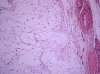

Case presentation: In this report, we describe the case of a 49-year-old Caucasian woman known for years to have fibrous dysplasia in the left femur and tibia who presented with progressive pain in her left leg and soft swelling in the left quadriceps region. After surgical intervention with excision of the soft-tissue mass, the diagnosis of Mazabraud's syndrome was confirmed. During follow-up, our patient presented with a painless mass located on the lateral side of the left knee, next to a second, intra-osseous lesion with the same characteristics in the left lateral tibial plateau. The histopathological examination was consistent with a soft-tissue intra-osseous myxoma.